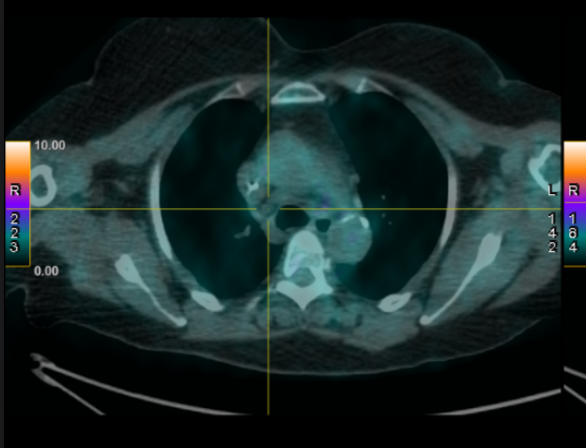

The PET-CT scan performed in April 2024 revealed a cavitary mass in the upper right lobe with intense hyperfixation (SUVmax 11) with several mediastinal and hilar lymphadenopathies; the most hypermetabolic lymph node was located in the Barety space (SUVmax 7.6).

Fig 1

Figure 1